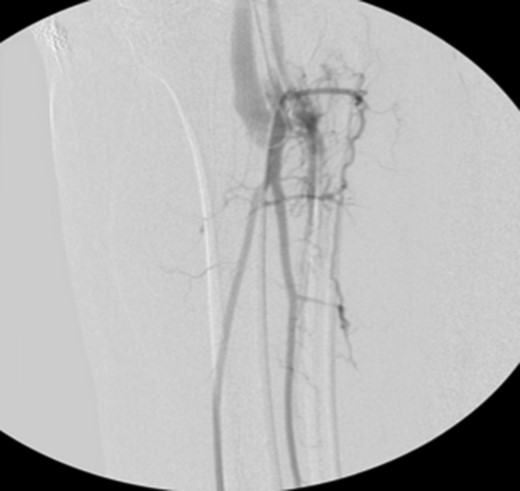

Patient underwent a left lower extremity angiogram. During the procedure she was found to have patent aorta and bilateral common iliac artery. There was no disease visualized in the left external iliac artery, common femoral artery (CFA), SFA, patent previously placed stent, patent above and below the knee PA and two vessel run off to the foot (Fig. 1). Upon delayed fluoroscopic images we identified contrast filling the deep venous system rather quickly suggesting a high volume fistula (Fig. 2). We then identified the fistula between ATA and ATV. Although ATA was previously ligated there was retrograde filling of the artery from unnamed branches, which communicated with the venous system as shown in. In the midcalf (ATA) was cannulated with a micropuncture needle. Micropuncture wire was inserted and a 5-Fr sheath was inserted after exchanging over wire. At this point VortX coils (Boston Scientific) were placed from the curve of ATA until the whole AVF was sealed. Anterograde angiogram showed no flow through the fistula (Figs 3 and 4). There was a palpable PT and DP pulse at the completion of the procedure. Sheath was removed, pressure dressing applied. Patient was discharged home same day. Recovery has been unremarkable. Three months follow-up claudication symptoms have significantly improved.

VortX coils (Boston Scientific) were placed from the curve of anterior tibial artery to its communication with venous system.